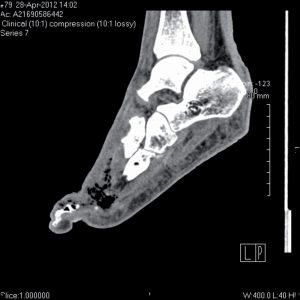

LA PLAIE DU PIED DIABÉTIQUE : Les clés du traitement

Dossier coordonné par le Dr Saïd Bekka (Chartres) et le Pr Patrick Ritz- Le traitement médical d'une plaie du pied diabétique :

les cinq clés – p. 266

Hélène Guermonprez (Lucé) - Ne pas "passer à coté" dudiagnostic du fasciite nécrosante

Cas clinique de plaies du pied diabétique– p. 275

Dr Marie-Christine Chauchard, Dr Muriel Alvarez (Toulouse)

Le traitement médical d’une plaie du pied diabétique – Les cinq clés

Le traitement d’une plaie du pied diabétique repose sur un ensemble de mesures thérapeutiques qui font appel à des spécialités très différentes. L’organisation des soins est fondamentalement médico-chirurgicale.

Ne pas « passer à côté » du diagnostic de fasciite nécrosante !

Dans notre secteur de diabétologie, deux patients diabétiques porteurs de plaies du pied ont dû bénéficier d’un geste de parage chirugical en urgence lors d’un même week-end. Ces patients étaient…